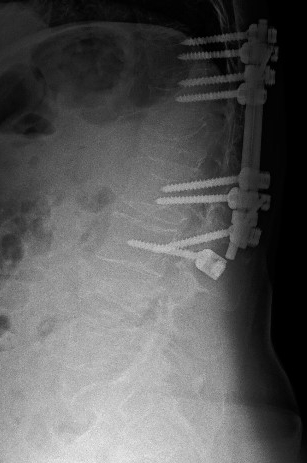

Direkt

grafilerde L4 vertebrasındaki kırık yanında, eski bir L1 kırığı

nedeniyle yerleştirilmiş olan T11-L3 transpediküler vida sisteminin

disfonksiyone olduğu görülüyor. L3 vidasında sağ tarafta muhtemelen

gevşemeye bağlı vida çıkması, solda ise vida başının roddan kurtulduğu

görülüyor.

Bilgisayarlı

tomografide L3 seviyesinde sağda vida gevşemesi (vida etrafında

sklerotik halo), L4 vertebrasında ön ve orta kolonda yükselik kaybı,

korpusa ve sol pediküle uzanan kırık hatları ve ayrıca bu

seviyede

solda belirgin olarak faset eklemlerde ayrışma görülmekte.

Sisteme ait diğer vidalar gevşememiştir. L2-3 seviyesinde kısmi,

yukarıdaki seviyelerde tam faset füzyonu vardır.